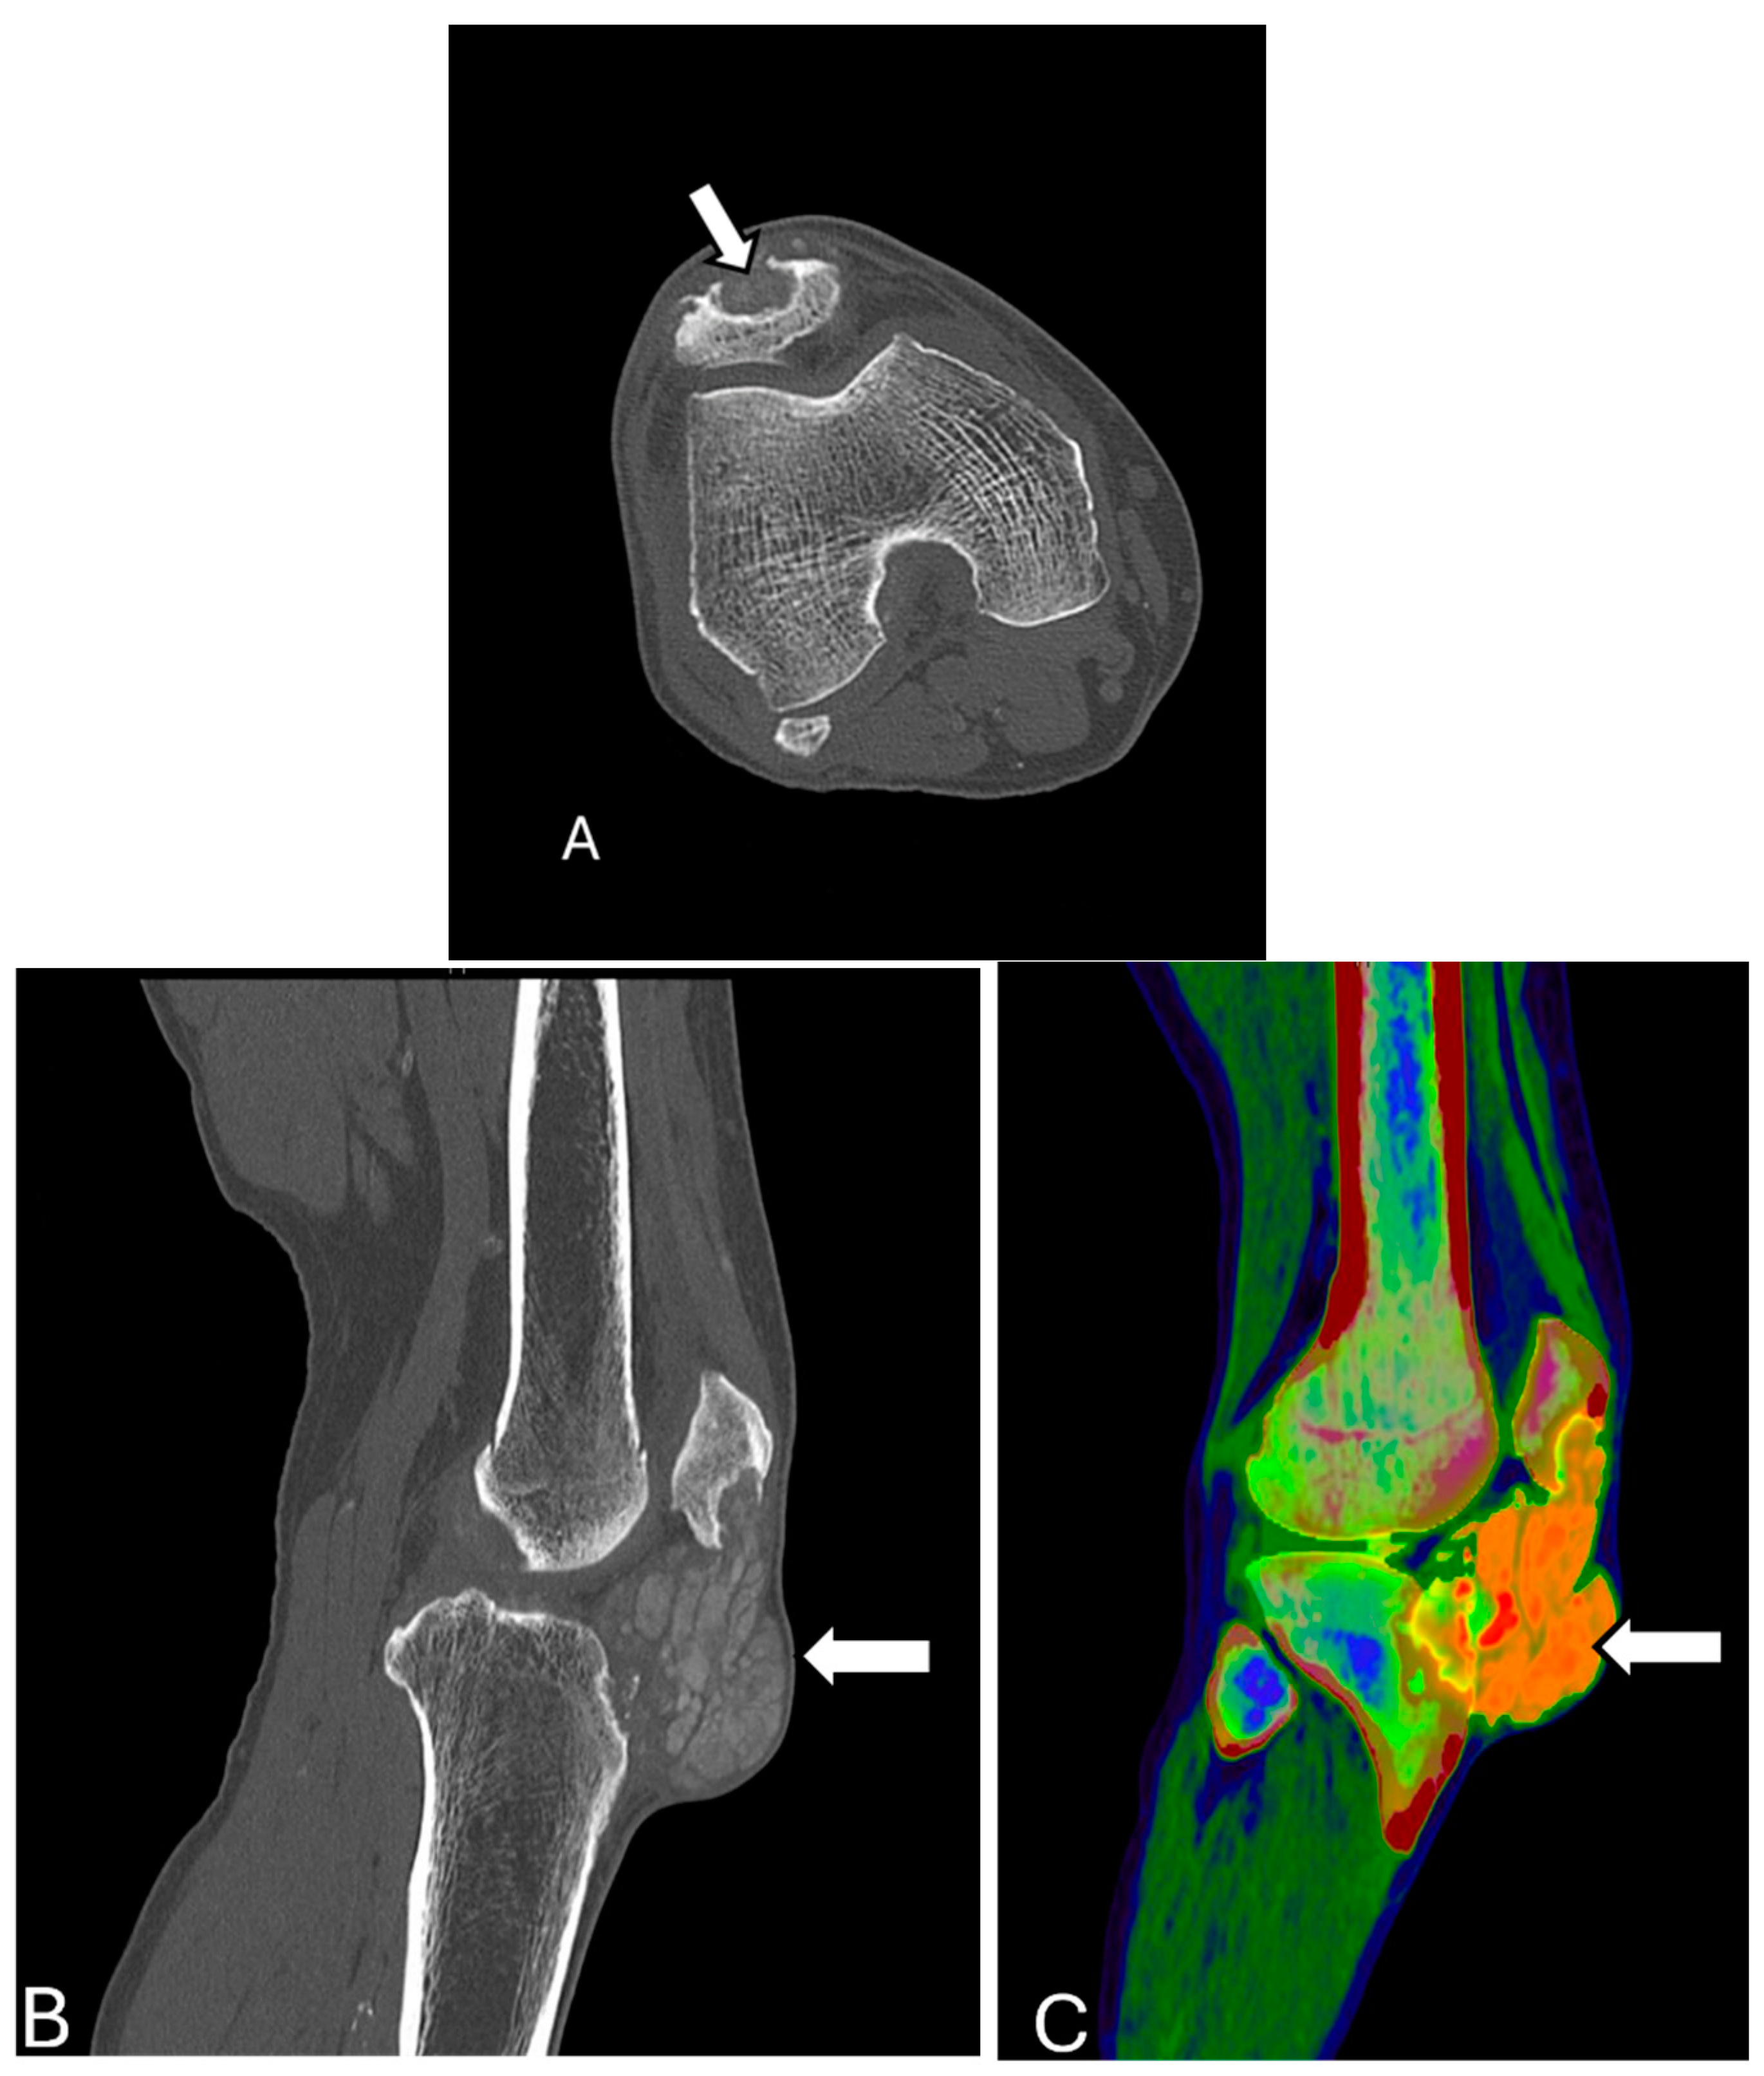

3.3. Osgood–Schlatter Disease and Sinding–Larsen–Johansson Disease

3.4. Osteochondral Injury